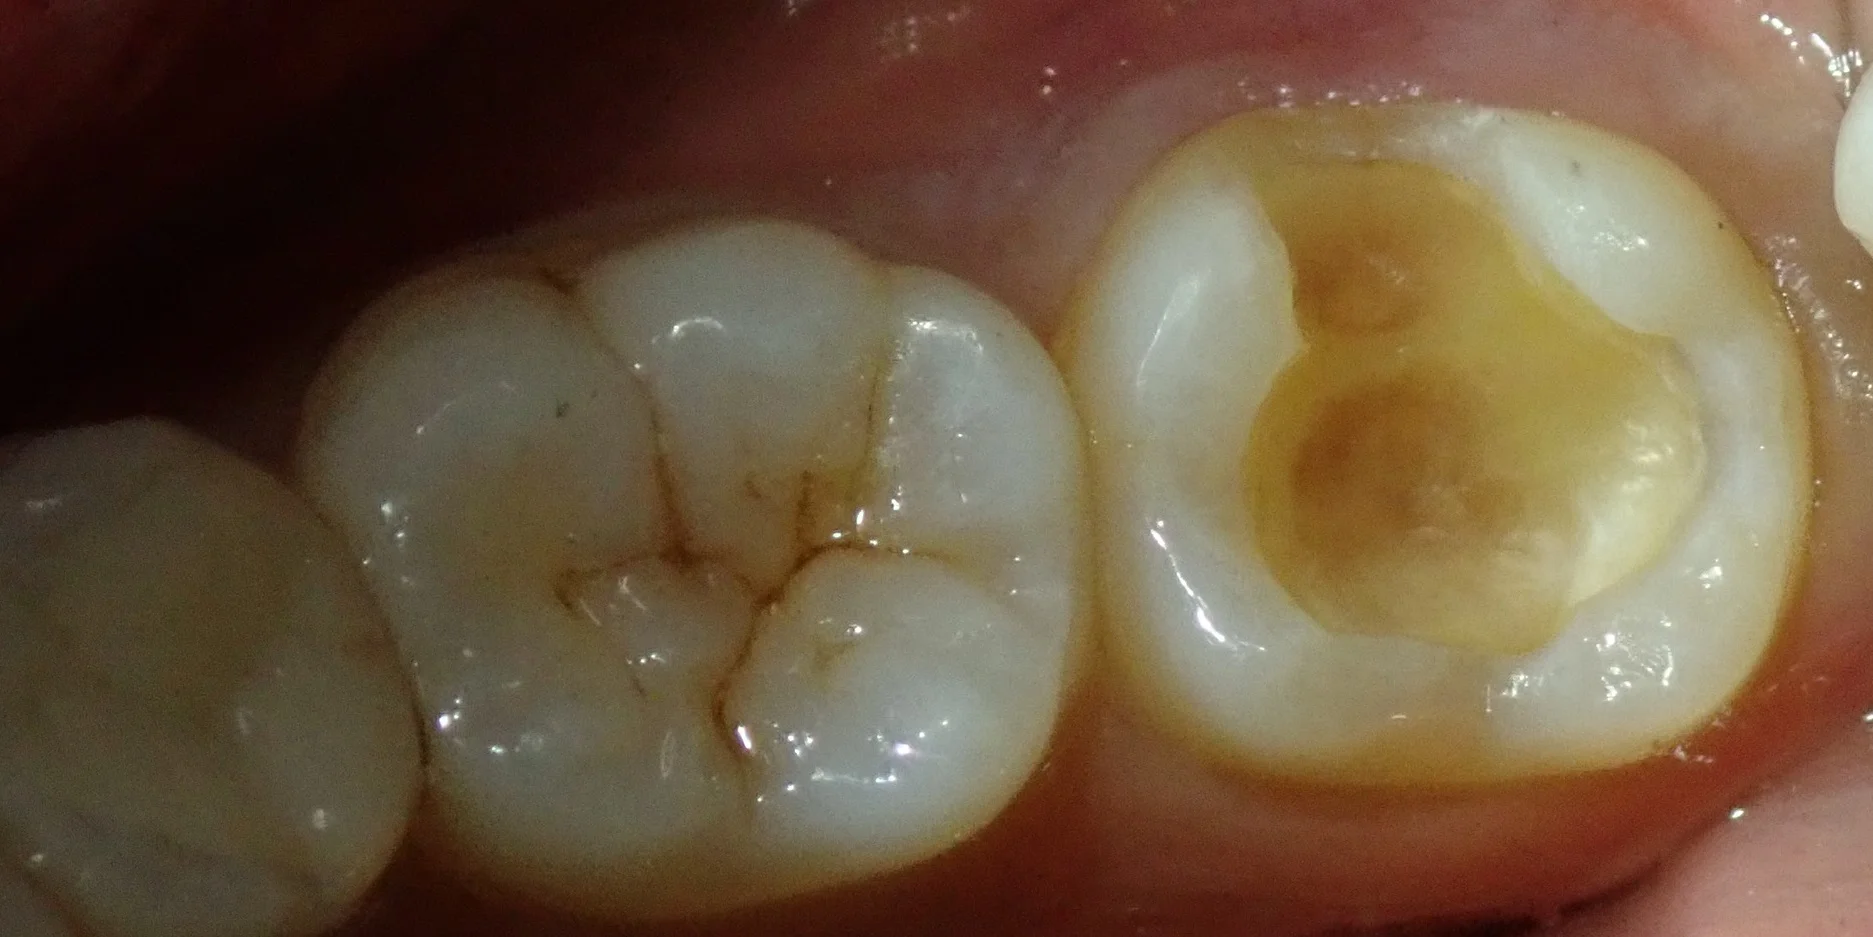

まずは術前ですね。

右側の金属が入っているところが今回治療に入る部分です。

レントゲン上で金属の下に虫歯があり、更に進行傾向が認められたため、今回治療介入することとなりました。

金属を外して、虫歯の除去が終わったのがこちらです。

うっすらと神経が見えかかっている状態です。

非常に大きな虫歯ではありましたが、無事に取りきることが出来ました。